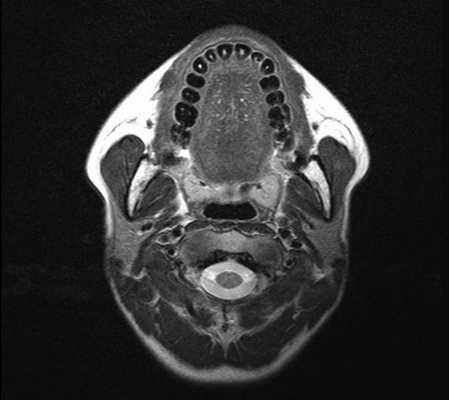

С помощью КТ сложно было выявлять опухоли малых размеров (Т1стадия) и их границы в результате низкой контрастности, а также новообразования с поверхностным распространением (рис. 1). Вместе с тем, 72,0% обследованных больных имели Т3, Т4 стадии опухолевого процесса и после болюсного введения контрастного вещества контрастность опухоли повышалась. С увеличением размера опухоли отмечалась неоднородность усиления из-за наличия некроза (рис. 2). Жировые пространства подъязычной области в нормальном состоянии представляют собой симметричную зону низкой плотности между челюстно-подъязычной и подбородочно-подъязычной мышцами. Облитерация жировых пространств подъязычной области служила основным показателем опухолевого поражения при выявлении небольших образований дна полости рта (рис. 3,4).

Сложно было выявлять опухоли малых размеров (Т1,Т2 стадии), расположенные в передних отделах дна полости рта из-за расположенных рядом костных тканей, зубов, наличия пломбировочного материала вследствие выраженных артефактов от плотных структур. В ряде случаев визуализацию облегчало наличие язвенного дефекта в структуре опухоли (рис. 5). При всех опухолях Т3, Т4 стадии определялось повышение плотности после введения контрастного вещества, их края четко визуализировались относительно окружающих тканей. Во всех случаях Т3, Т4 стадии удавалось определить размер опухоли и оценить инфильтрацию и распространение в соседние зоны, а также за среднюю линию (рис. 6).

Особенностью МРТ являлась высокая контрастность мягких тканей. Плотные костные ткани или зубоврачебный материал не создавали артефактов, что давало возможность получать четкое изображение опухоли полости рта, определять распространение в мягкие ткани, глубокие отделы орофарингеальной зоны, в область неба. На Т1-ВИ все опухоли имели ту же интенсивность сигнала, как у окружающих мышц или слабее (рис.7).

Киста слюнной железы на МРТ полости рта (аксиальная проекция)